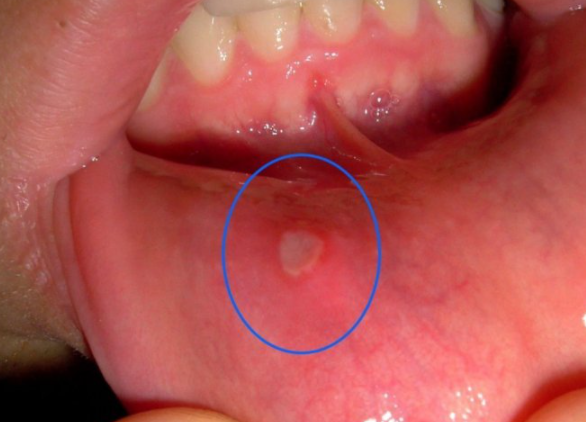

Bijele i vrlo iritantne ranice u ustima koje peckaju i bole u dodiru s jezikom ili hranom zovu se afte. Ako ste skloni aftama, a želite ih se riješiti čim prije, donosimo četiri prirodna lijeka koje možete napraviti sami

Afte su bijele ranice u ustima koje mogu biti vrlo neugodne i bolne, posebno ako ih dotaknete jezikom ili hranom.

Iako nisu zarazne niti opasne za zdravlje, njihovo peckanje je vrlo iritantno, a zbog toga što su stalno vlažne od sline, proces zacjeljivanja je vrlo spor.